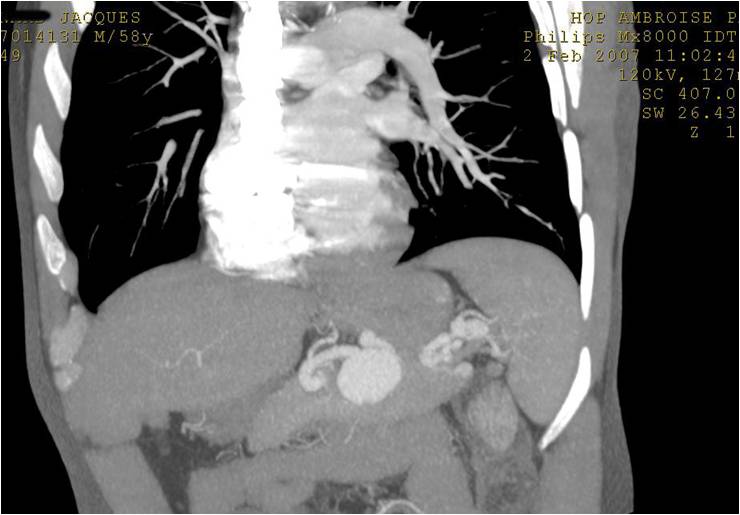

末端动脉阻塞(end-artery occlusion)

末端动脉栓塞:医源性肾损伤-移植肾活检

活检后动脉瘤破裂 |

微导管在载瘤动脉末端 |

载瘤动脉末端栓塞 |

Coil=3 |